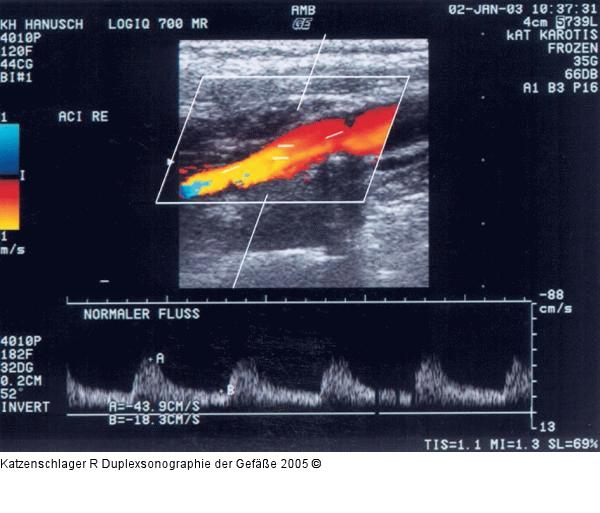

Abbildung 3: Duplexsonographie - Karotis

Normalbefund der A. carotis interna |